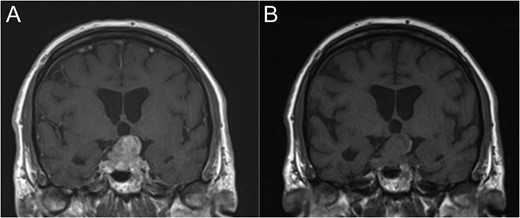

Coronal T1-weighted MRI with (A) and without (B) Gadolinium contrast enhancement.

By far the most likely diagnosis at representation would be a recurrence of the original adenoma. If malignancy elsewhere was known, then a metastasis may have been considered. Given this was a de novo presentation of metastatic lung carcinoma, the diagnosis was something of a surprise.